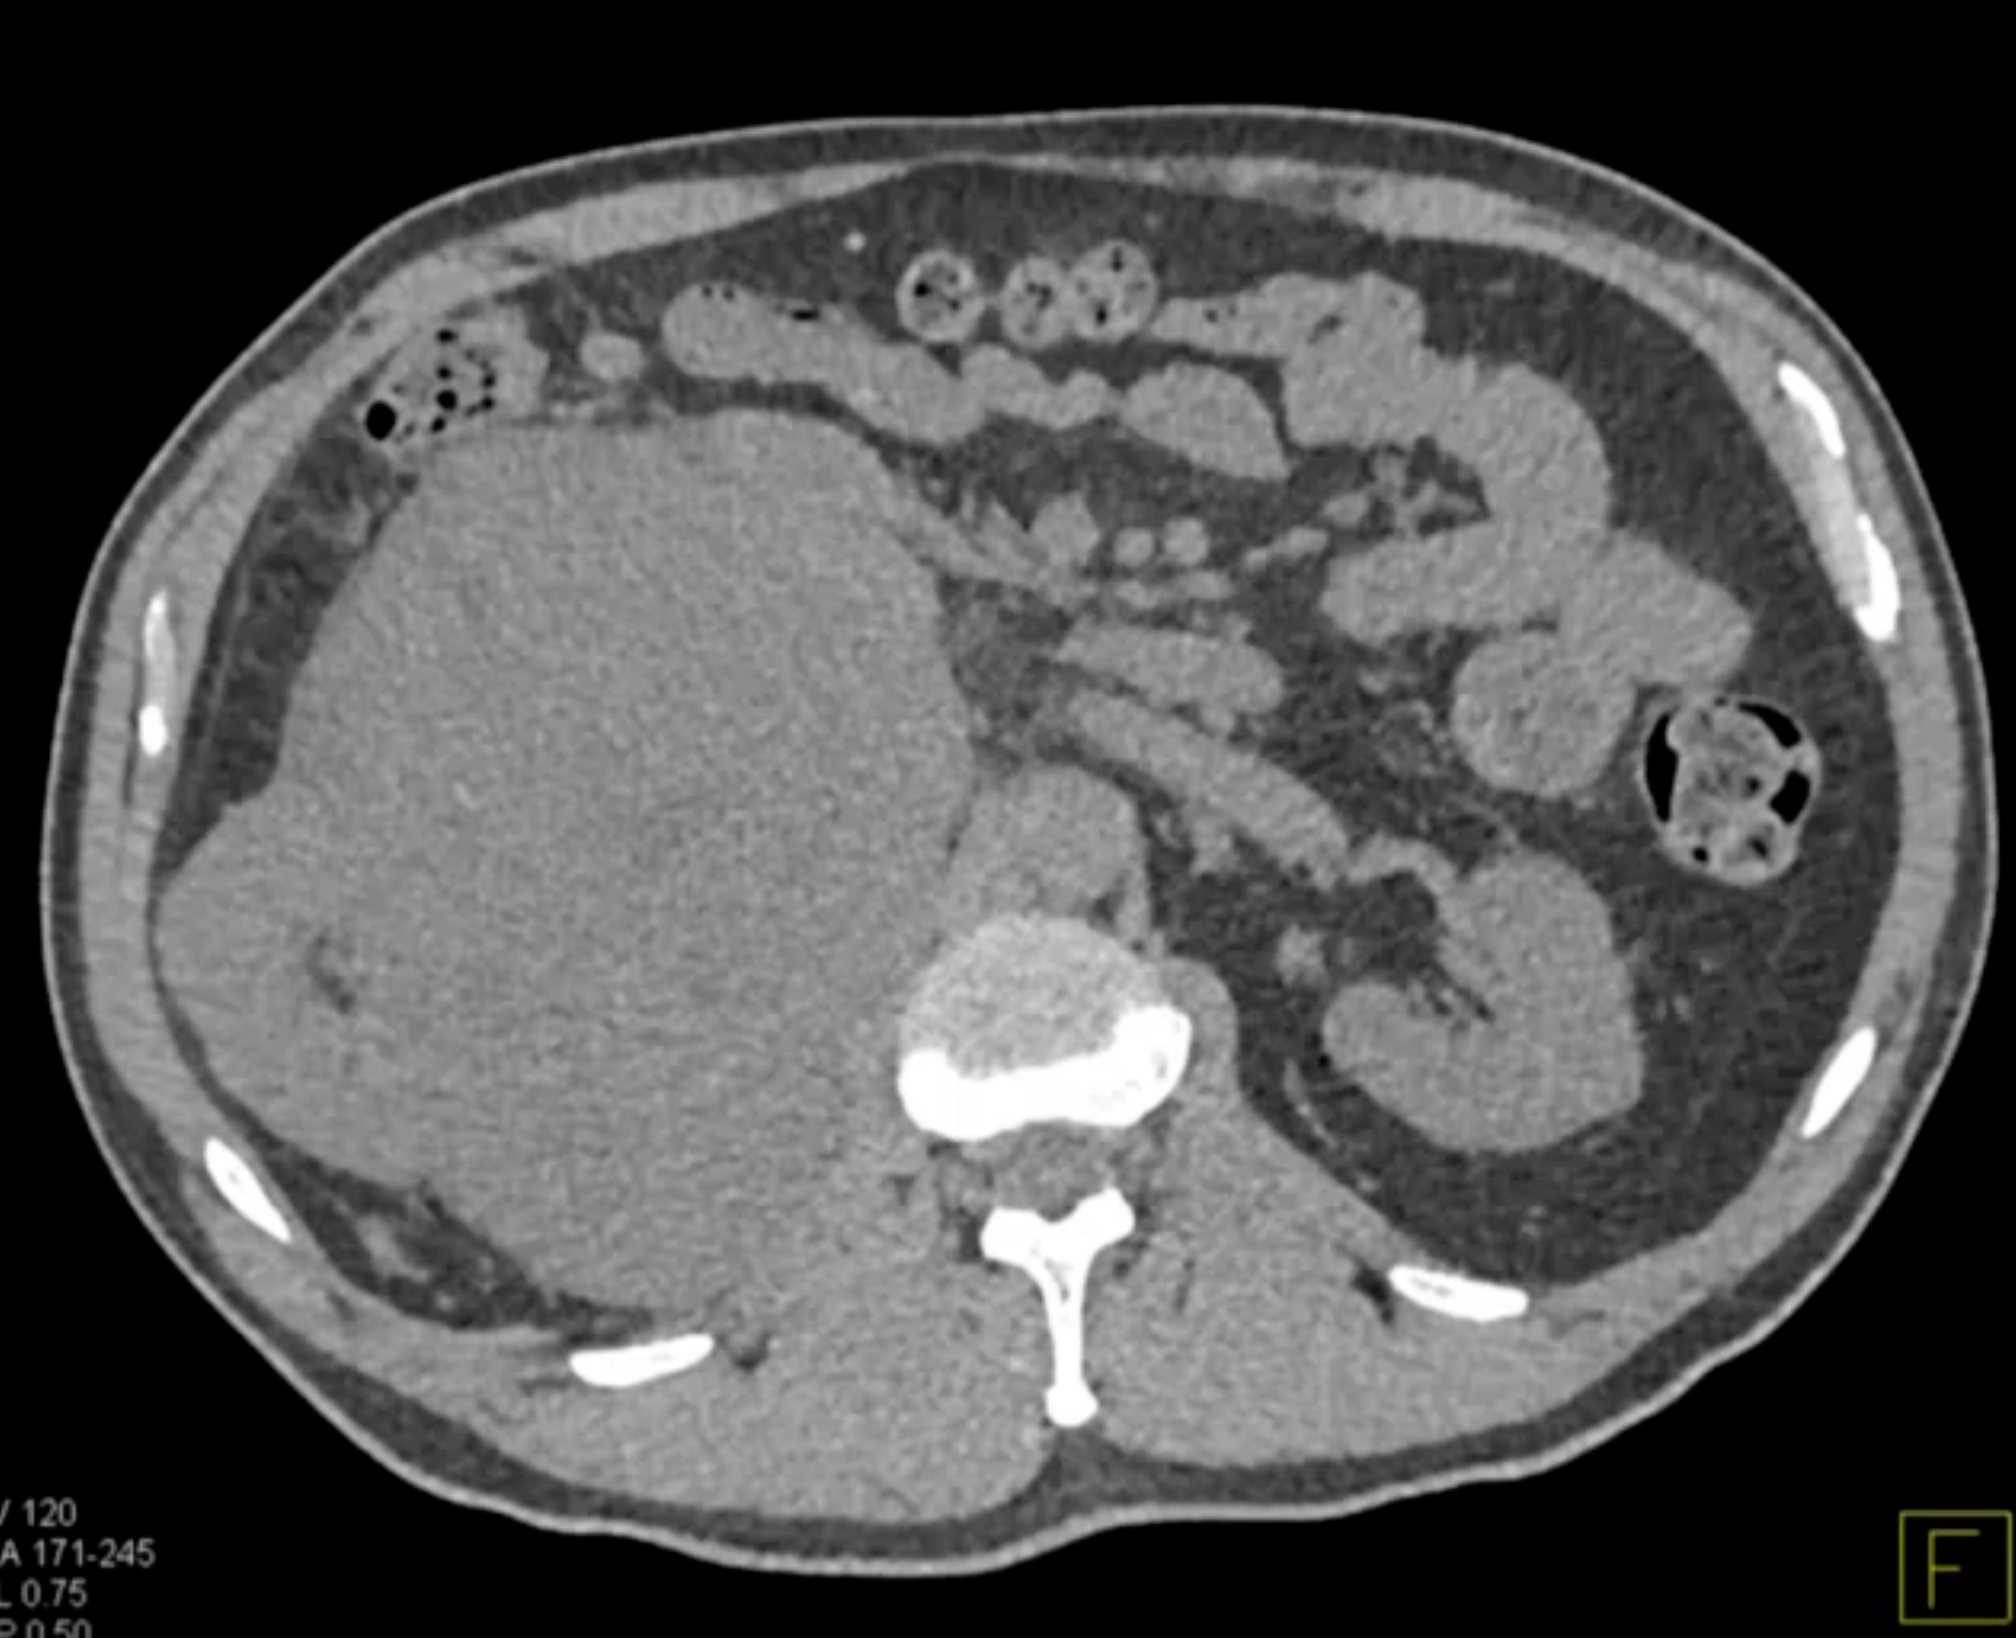

Left Adrenal Metastases from Renal Cell Carcinoma